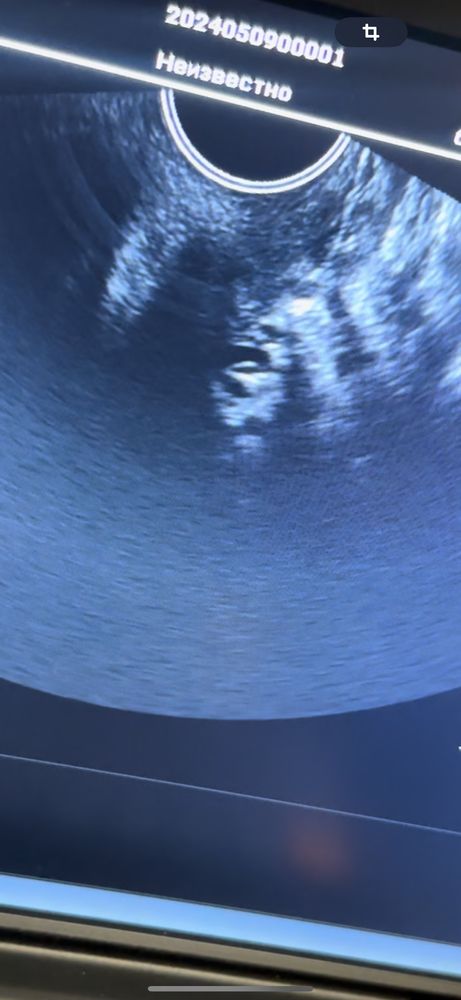

Здравстауйте, когда лучше идти на первое узи? 8 день задержки, 4 мая сдавала хгч, был 2873, сегодня сходила на узи, вагинально она увидела, а через живот не очень, страшно прям

На канун хгч 2670 был, по животу пя 4,5 мм, вагинально 7 мм. Все зависит от уровня хгч, узиста и аппаратуры. Меня смотрели на 4,6 акушерских недель (овуляция была на 12 день цикла, сам цикл 28 дней)

Не зря же на ранних сроках смотрят вагинально. У меня на 8й неделе через живот все отлично было видно, раньше не пробовала

На таком сроке через живот увидеть, думаю, не реально, может у кого-то и было видно, но у меня и моих знакомых первое (да и на 6-7 неделях) смотрели вагинально только. Через живот не было видно. Так что, если вагинально увидели беременность, значит она есть)